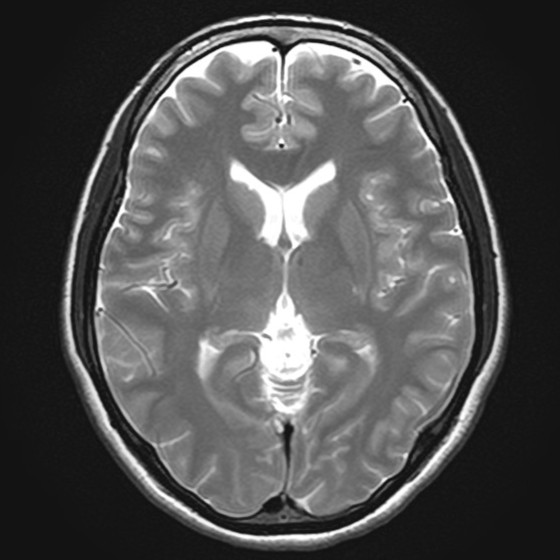

当院ではVSRAD(ブイエスラド)というアプリケーションを用いて、同年代の正常脳と比較して、海馬(かいば)がどの程度委縮しているかを統計的に解析し評価することができます。

アルツハイマー型認知症では、この海馬の萎縮が関係しており、早期のアルツハイマー型認知症の診断に役立てています。